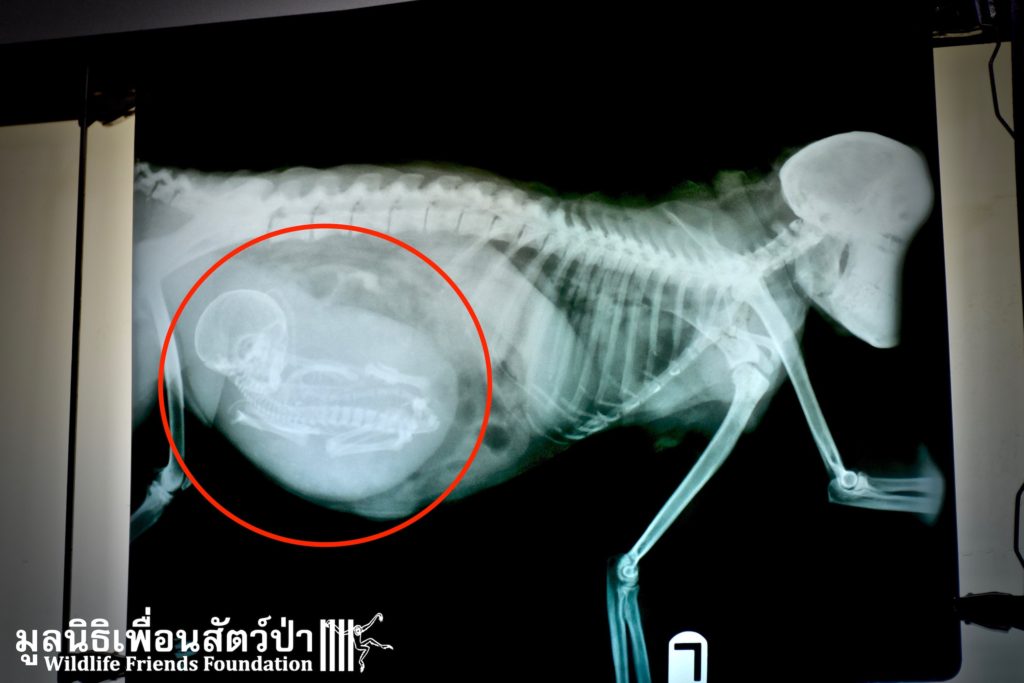

Yesterday we received a telephone call from a concerned resident in Hua Hin, who had found a severely injured female long-tailed macaque (Macaca fascicularis) next to a garbage collection area at the side of a busy road. The WFFT Wildlife Rescue Team headed straight to try and save this monkey. Open arrival to the scene they found a very weak, almost unresponsive macaque on the ground. We do not know why she was found in such a weakened state, she may have been involved in a road traffic accident, or be suffering from an illness. She was loaded on the rescue vehicle and rushed straight to an animal x-ray clinic to help the vet team properly diagnose the problem. She was then transported to the WFFT Wildlife Hospital for further assessment and treatment.

We have named this macaque Chomsin, after the road she was found on. Upon arrival to the WFFT Wildlife Hospital the vet team performed an ultrasound to check on the health of the unborn infant. Sadly, the ultrasound reveled that the infant was dead. Chomsin was rushed into emergency surgery to perform an abortion in the hope that we could at least save her life. The infant was successfully removed and less than 24 hours later, Chomsin is now sat up eating and drinking. However, this does not mean she is out of the woods yet, we will only be able to tell over the next few days if she will make it, and if she does she will be released back to the wild. We will keep you posted on her progress.